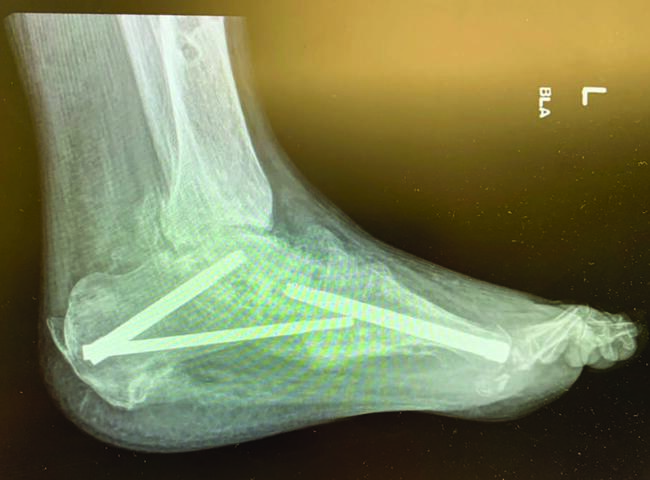

William P. Grant, DPM popularized the concept of beaming in Charcot,2 and subsequent modification and perfection continues through more recent literature.3 Beaming the medial column with large diameter screws was first mentioned at the American College of Foot and Ankle Surgeons conference in 1997.4 Since then, literature supports 2 to 3 beams in the medial and lateral columns, and the hindfoot for more stability.2 Beaming the midfoot and hindfoot acts like reinforcement rods, or rebar, to accept compressive and tensile loads and compensate for inadequacies of native structures.

Grant and colleagues looked at beaming of the medial column only versus medial and lateral with and without subtalar joint arthrodesis.2 They found that with medial column beaming alone, the mechanical advantages of the posterior tibial tendon increased, which led to increased plantar lateral pressure and collapse of the non-beamed lateral column. They also found that locking the subtalar joint (via either arthrodesis or arthroereisis) further stabilized transverse and frontal plane torsion.2 Other studies confirmed that this 3-beam construct seems to be the most stable, with less chance of a secondary collapse in the foot.3,5 Other advantages of beaming include no cortical stress on the bone (unlike plates/screws), allowing for fixation beyond the site of collapse, making it more stable, and no exposed hardware in the presence of dehiscence.3

Regarding weight-bearing, studies with patients in an external fixator with beaming were allowed to walk, but those without an external fixator underwent non-weight-bearing for 2 to 3 months. Solid stainless steel screws are the strongest construct, as they provide more tensile strength than titanium. Furthermore, most studies involving beaming additionally perform an adjunct Achilles or gastrocnemius lengthening procedure for equinus, a common concomitant issue in feet with Charcot changes.3